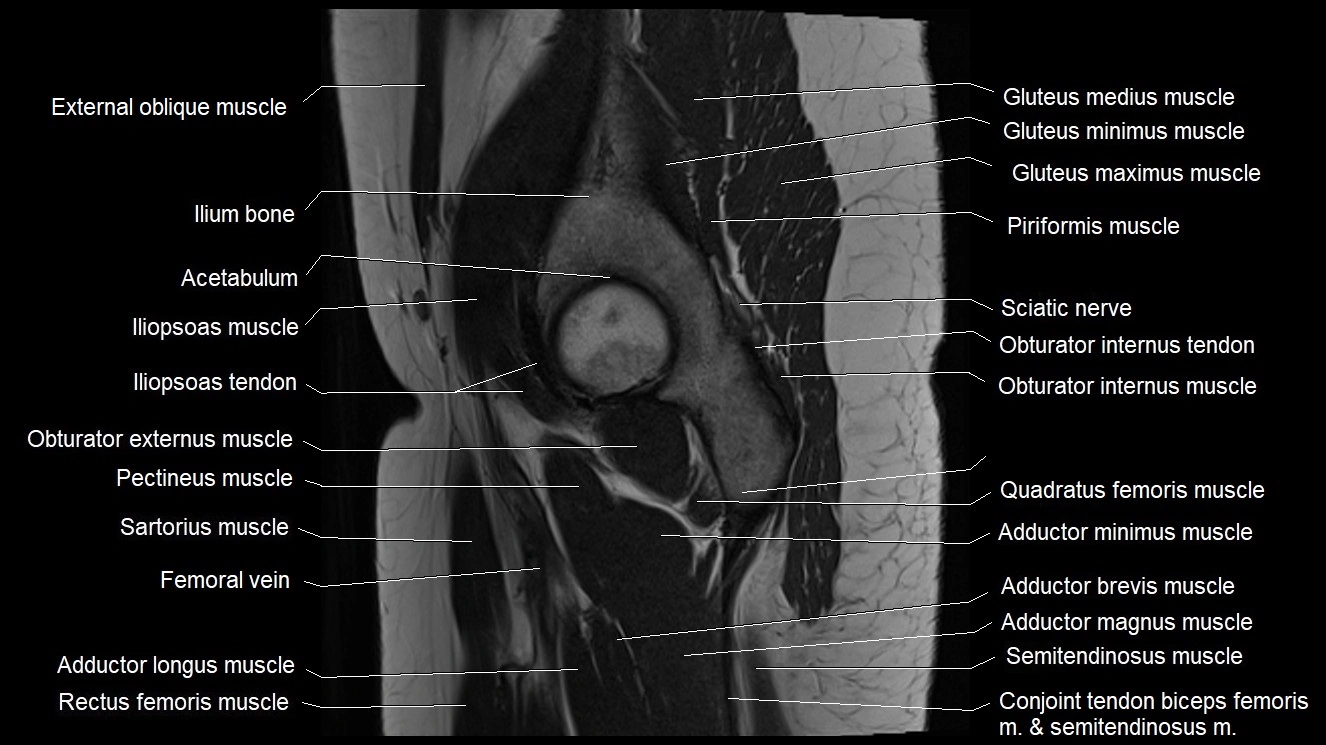

- Acetabulum

- Gluteus medius muscle

- Gluteus minimus muscle

- Gluteus minimus tendon

- Iliopsoas muscle

- Iliopsoas tendon

- Iliotibial tract

- Ilium bone

- Inferior gemellus muscle

- Obturator internus muscle

- Obturator internus tendon

- Pectineus muscle

- Quadratus femoris muscle

- Rectus femoris muscle

- Sartorius muscle

- Semimembranosus tendon (proximal)